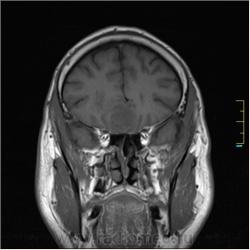

Пациентка направлена на исследование с диагнозом "Гипертонический криз", энцефалопатия неуточненная.

Cor T1:

частично функционирующая аневризма

Иначе говоря, аневризма с хронической геморрагией, т.к. мы видим фракции крови различного возраста.

По-моему, аневризма с пристеночными тромбами.

Постепенное пристеночное образование тромбов приводит к появлению типичного для аневризмы феномена -слоистости МР сигнала в полости аневризмы. Данная картина демонстрирует слоистый характер тромботических масс в полости аневризмы .Функционрирующая часть имеет низкий сигнал во всех режимах сканирования. Дополнительно-перифокальный отек.

А может более корректно интерпретировать как частично тромбированная аневризма... Уж коь речь идет о фракциях, ну то есть о тромбе по сути.... Ну и плюс перфокальный отек головного мозга (вероятнее цитотоксический+вазогенный).